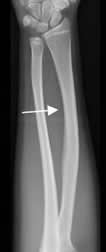

Fig 66. Deformidad plástica.

Rx AP. Presencia de curvatura lateral en la diáfisis del radio, por deformidad plástica.